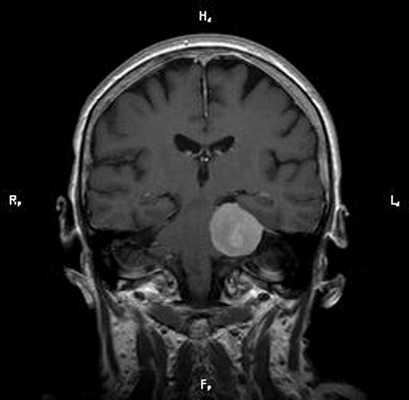

Проблема: жалобы на частые головные боли, снижение слуха (левое ухо), а также шум в ушах (больше слева). Пациент был направлен на МРТ головного мозга в ЦМРТ с целью уточнения диагноза.

Диагноз: Онкология. Менингиома мосто-мозжечкового угла

При МРТ головного мозга в левом мосто-мозжечковом углу определялось больших размеров округлой формы внемозговое патологическое образование, с четкими ровными контурами, широким основанием, прилежащее к твердой мозговой оболочке. После внутривенного контрастирования отмечалось равномерное, выраженное усиление интенсивности МР-сигнала от вышеописанного образования, а также твердой мозговой оболочки. Пациенту был поставлен диагноз (менингиома левого мосто-мозжечкового угла).